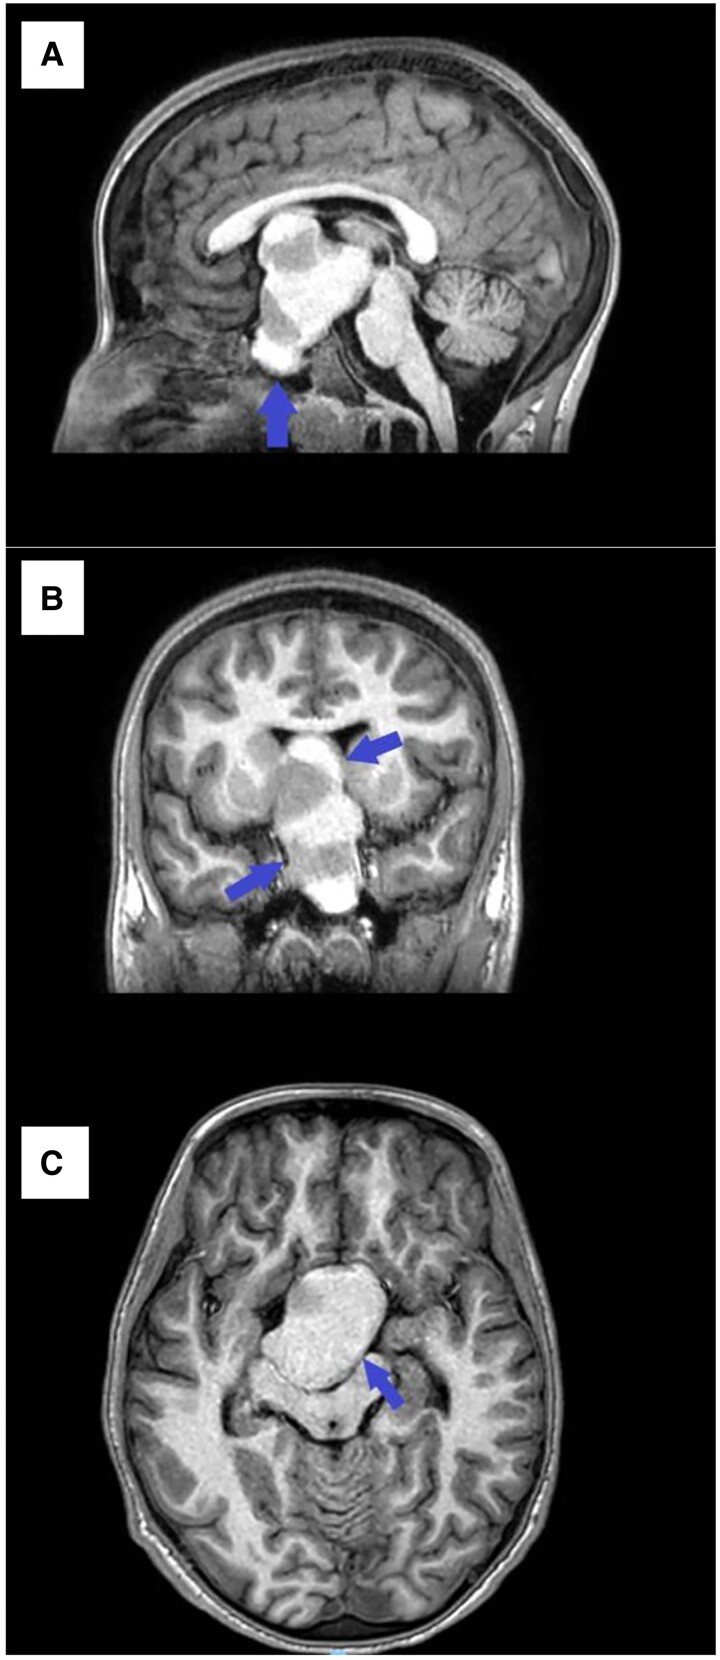

Pituitary gigantism (PG) is a rare endocrine disorder that may present with multiple pituitary hormone abnormalities in pediatric patients. A hallmark presentation is accelerated growth due to growth hormone (GH) excess. Current treatment modalities include surgery, radiation, and medical therapy. We describe a 14-year-old girl who presented with recurrent slipped capital femoral epiphysis with GH excess and multiple other hormonal abnormalities. A sellar mass was identified on magnetic resonance imaging of the brain and was surgically resected. The pathology report was consistent with pituitary gland adenoma with mammosomatotrophs hyperplasia. Post surgery, serial laboratory results showed persistently elevated growth factor and GH levels, and residual tumor was reported on follow-up imaging. Even though we found limited data on the efficacy and safety of a long-acting somatostatin analogue, lanreotide, in the treatment of PG, a total of 4 doses of lanreotide successfully reduced growth factor and GH levels to normal ranges in our patient. Repeat imaging 5 weeks post discontinuation of lanreotide showed reduction of residual tumor volume. This case reveals that a short course of lanreotide may be used as an effective medical treatment in pediatric patients with PG who have residual disease after surgical intervention.